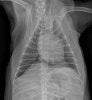

수술 전 흉부 방사선검사 / 출처: 라온동물메디컬센터

수술 전 검사에서 전신 상태 및 마취에 무리가 없음을 확인한 후 수술을 진행하였습니다.